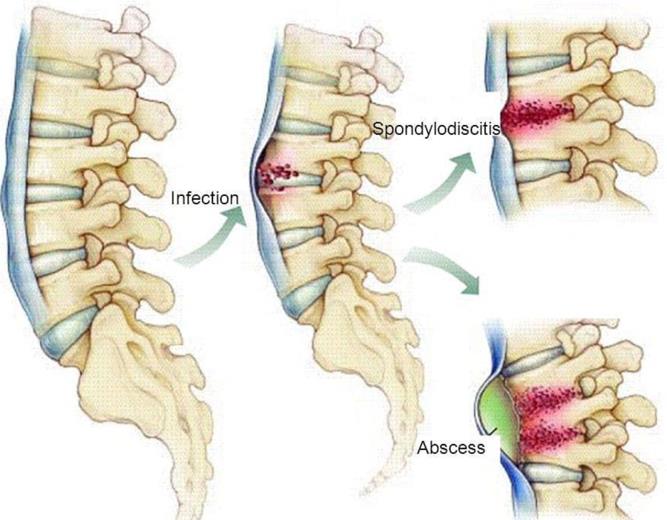

3. Espondilodiscitis

¿Qué son las Espondilodiscitis?

Son infecciones que aparecen en la columna del niño. Se producen en el niño como consecucencia de la existencia de una infección en otro lugar del organismo que produce una suelta de gérmenes al torrente sanguíneo y posteriormente se depositan en diferentes lugares del organismo entre ellos en la columna y el disco intervertebral. El disco no recibe vascularización y como consecuencia de ello pueden desarrollarse fácilmente los gérmenes produciendo una destrucción del disco y de las vértebras superior e inferior al disco (Fig 3).

¿Qué sintomatología tienen las Espondilodiscitis?

La sintomatología depende en función de la agresividad del germen. Si la destrucción del disco es lenta, puede pasar desapercibida mucho tiempo o muy rápida por un germen más agresivo como es en la mayoría de los casos de los niños, en los que la sintomatología es más llamativa.

El dolor le impide al niño deambular y se acompaña de otros signos como son el decaimiento, dolor nocturno que impide el descanso y fiebre. En ocasiones el paciente puede estar muy afectado clínicamente por un cuadro séptico.